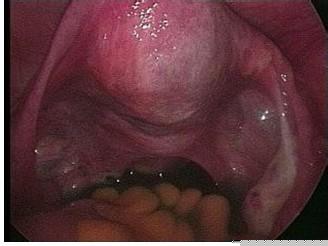

宮頸糜爛常見(jiàn)癥狀

宮頸糜爛的出現(xiàn)對(duì)女性所造成的危害是很大的,但很多女性對(duì)宮頸糜爛都沒(méi)能以...[詳細(xì)]